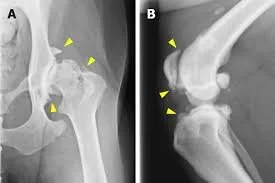

Hip Dysplasia in Dogs: Symptoms, Causes, and Treatment

Hip dysplasia is a common cause of pain and limping in dogs, especially in large breeds. Learn how to recognize the signs and what treatment options are available.